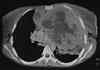

Patología mediastínica